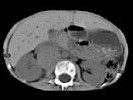

- 多项选择题男孩,5岁。消瘦、贫血、纳差和腹部包块3个月余, CT如图所示,下列说法正确的是

A、右侧腹腔内可见一巨大软组织肿块影,其边界欠清楚

B、肿块密度不均匀,可见片状的较高密度,考虑为出血,也可见点状的钙化影

C、该病灶来源于肝脏,考虑为肝母细胞瘤

D、该病灶来源于右肾上腺,考虑为神经母细胞瘤

E、该病灶来源于右肾,考虑为肾胚胎瘤